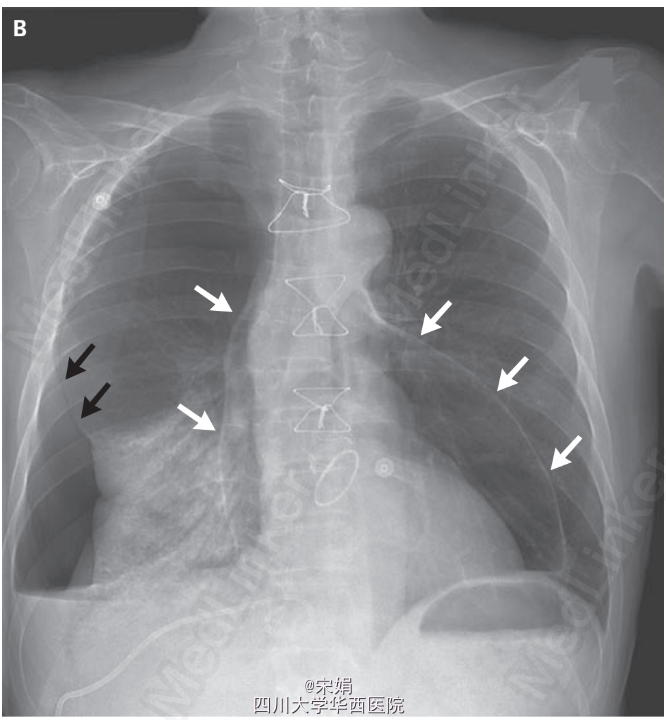

声引导下置入猪尾巴管引流胸腔积液,共引流2.8升渗出液。操作后复查胸片(图B)显示右侧大量气胸(黑色箭头)伴下叶肺不张,同时还有大量心包积气(白色箭头)。继续进行经皮引流,随后使用抗炎药物以及秋水仙碱治疗心包切开术后综合征(postpericardiotomy syndrome)*。患者病情痊愈后出院。